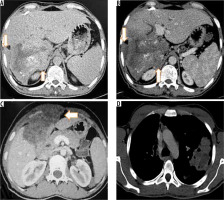

Figure 7

T2-weighted axial (A) and corresponding T-weighted magnetic magnetic resonance (MR) image (B) reveals solid hypointense peripheral lesion in segment VII. Post-contrast volumetric interpolated breath-hold examination (VIBE) MR image in arterial (C) and portal venous phase (D) reveals absence of contrast enhancement